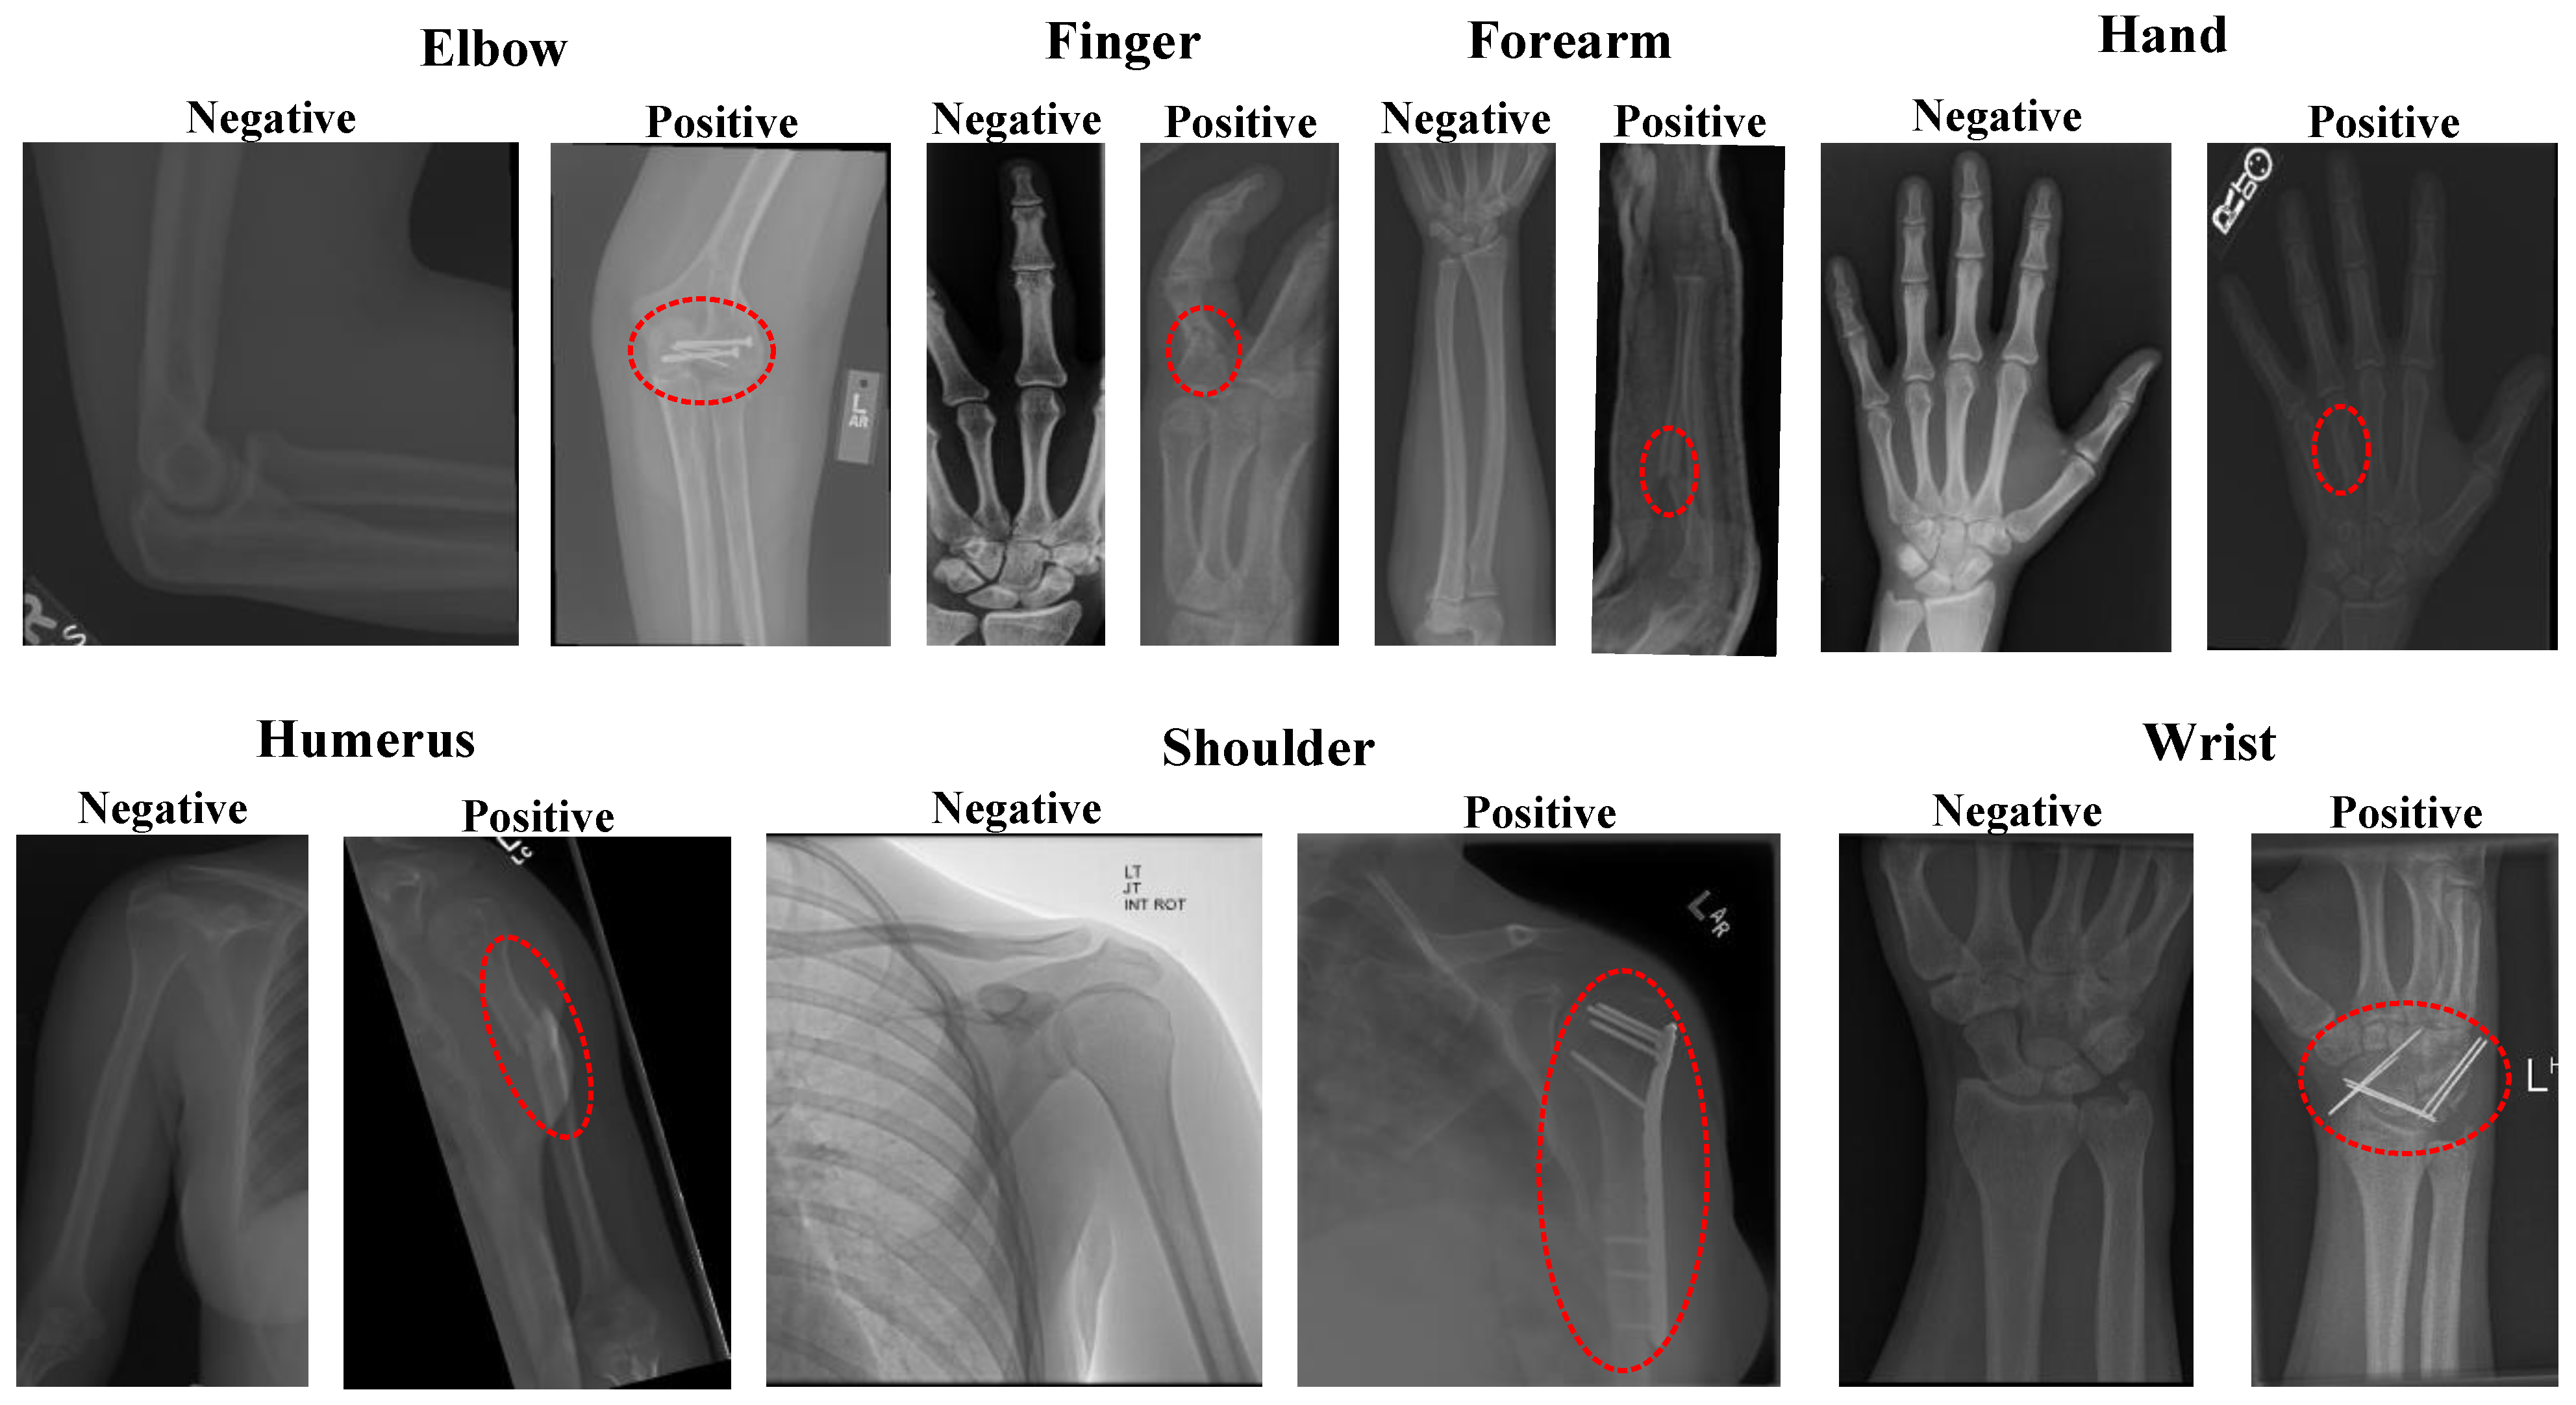

2.1. Dataset

- Rajpurkar, P.; Irvin, J.; Bagul, A.; Ding, D.; Duan, T.; Mehta, H.; Yang, B.; Zhu, K.; Laird, D.; Ball, R.L. Mura: Large dataset for abnormality detection in musculoskeletal radiographs. arXiv 2017, arXiv:1712.06957. [Google Scholar]

| Classes | Accuracy (%) | Specificity (%) | F1-Score (%) | Recall (%) | Precision (%) | |

|---|---|---|---|---|---|---|

| Elbow | Negative | 92.04 | 86.18 | 93.45 | 96.10 | 90.94 |

| Positive | 96.10 | 89.86 | 86.18 | 93.87 | ||

| Finger | Negative | 91.19 | 87.45 | 92.88 | 93.53 | 92.24 |

| Positive | 93.53 | 88.44 | 87.45 | 89.45 | ||

| Forearm | Negative | 92.11 | 84.57 | 93.97 | 96.39 | 91.67 |

| Positive | 96.39 | 88.59 | 84.57 | 93.01 | ||

| Hand | Negative | 91.34 | 76.28 | 94.25 | 96.85 | 91.78 |

| Positive | 96.85 | 82.51 | 76.28 | 89.84 | ||

| Humerus | Negative | 91.35 | 88.15 | 92.02 | 94.21 | 89.93 |

| Positive | 94.21 | 90.57 | 88.15 | 93.12 | ||

| Shoulder | Negative | 89.49 | 87.81 | 89.70 | 91.14 | 88.31 |

| Positive | 91.14 | 89.26 | 87.81 | 90.75 | ||

| Wrist | Negative | 92.63 | 88.74 | 93.86 | 95.32 | 92.45 |

| Positive | 95.32 | 90.78 | 88.74 | 92.91 | ||